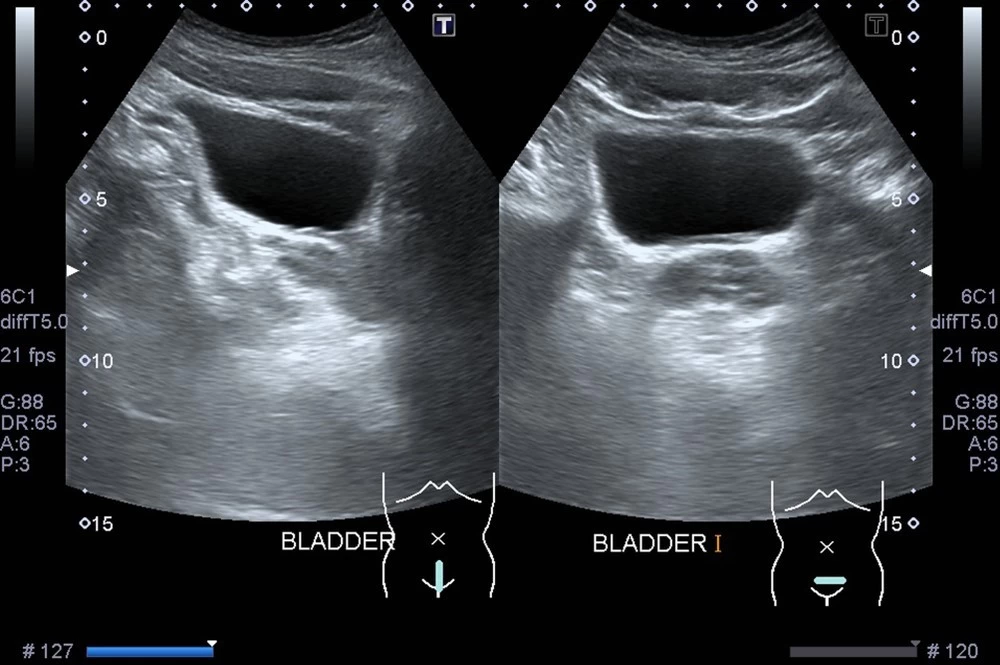

Ультразвук обеспечивает четкое изображение стенок органа, формы, размера и наличия каких-либо отклонений. Его можно выполнить двумя основными вариантами: трансабдоминально (через низ живота) и внутренним доступом (через влагалище у женщин). Трансабдоминальный подход используется чаще и особенно полезен для оценки объема остаточной мочи и наполненного пузыря.

Подготовка к УЗИ мочевого пузыря необходима для повышения информативности обследования. При УЗ-осмотре наружным датчиком через надлобковую область позаботьтесь о достаточном наполнении: в растянутом до объема 180-220 мл мочи будут более точно визуализироваться нарушения строения стенки или объемные образования полости. Задержка мочи может быть вызвана различными состояниями, включая увеличенную простату, стриктуры уретры или повреждение нервов, влияющее на функцию мочевого пузыря.

- Визуализация: Врач УЗИ перемещает датчик по нижней части живота. Устройство посылает звуковые волны в тело, и эти волны отражаются от мочевого пузыря и других структур, создавая изображения на экране.

- Визуализация после мочеиспускания: после получения первоначальных изображений пациента могут попросить опорожнить мочевой пузырь, и будут сделаны дополнительные изображения для измерения оставшейся мочи.